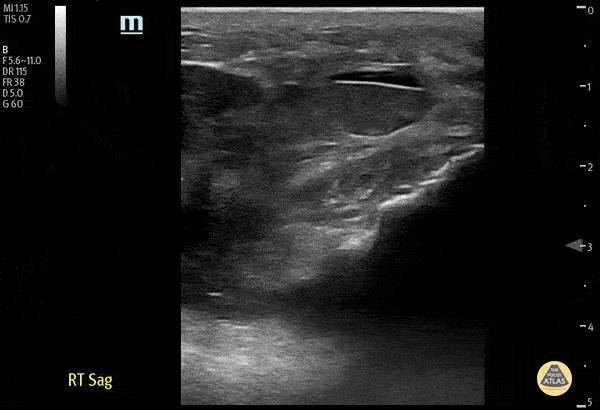

70 y/o male fell onto his right knee presented with visible deformity of the distal quadriceps muscle. Physical exam demonstrated weakness to active extension of the right knee. POCUS with a linear transducer demonstrated complete loss of tendon architecture of the right knee, including a hypoechoic defect between the tendon fibers. When compared to normal knee radiographs, the patient has significant displacement of the patella distally. Radiologists interpreted this as possible quadriceps tendon rupture. During operative repair, a complete rupture of the quadriceps was discovered and repaired. Justin Morin, DO PGY-1 @justinjmorin; Alex Schlangen, DO PGY-1; Lauren Lowes, DO PGY-3; EM Residents at Central Michigan University